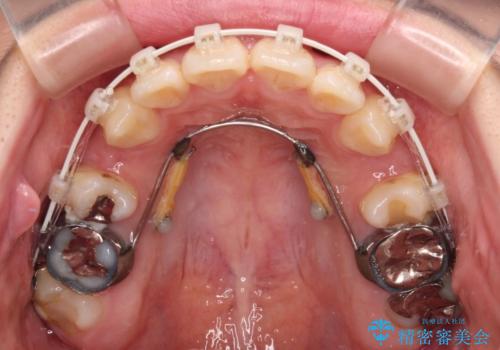

突出感の強い上顎前歯をしっかりと後方移動させるため、上顎の裏側の補助装置(リンガルアーチ)とアンカースクリューを併用しています。

上下左右の第一小臼歯を抜歯して、目立ちにくいワイヤー装置で矯正を行いました。